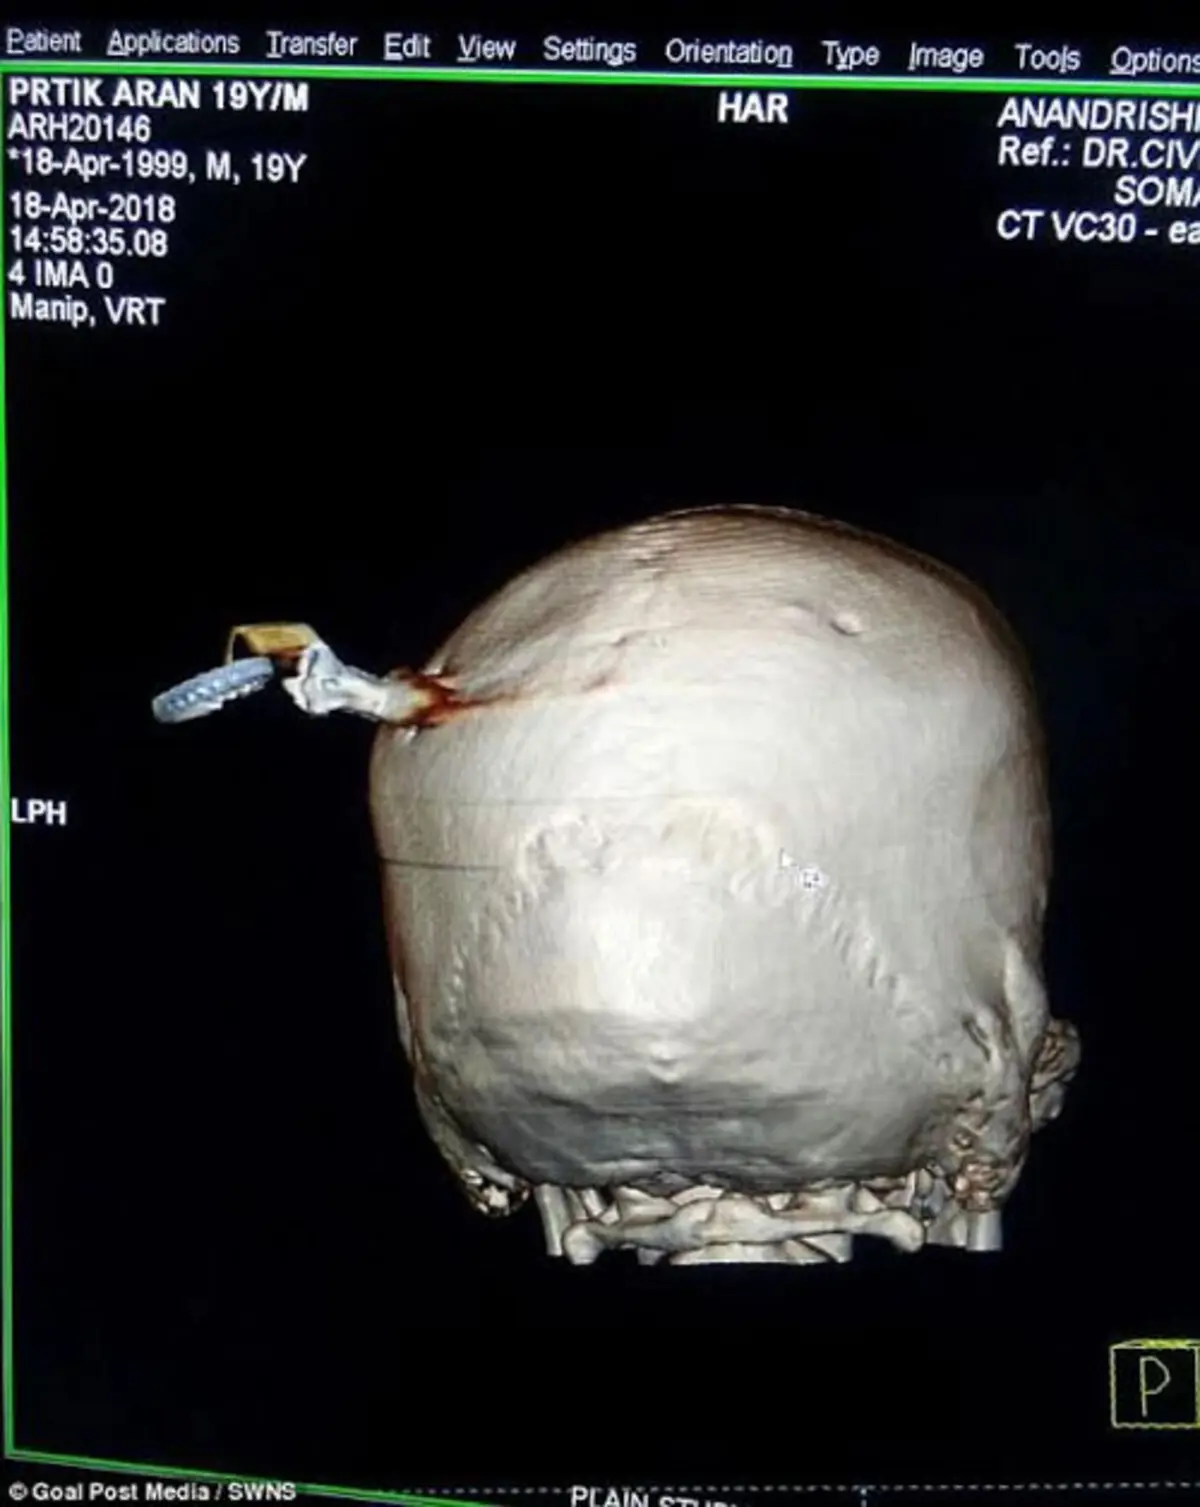

شاب يصدم الأطباء بمفتاح دراجة نارية في جمجمته (صور)

نُقل شاب إلى المستشفى بمفتاح دراجة نارية داخل جمجمته بعد مشاجرة عنيفة في الهند.

وأجرى الجراحون المصدومون جراحة دامت 3 ساعات ونصف، بعد نقل الشاب البالغ من العمر 19 عامًا من ولاية "ماهاراشترا" الهندية إلى المستشفى، لإزالة مفتاح اخترق جمجمته بعمق بوصتين.

وعولج الشاب في مستشفى "أناند ريشي" وخضع لجراحة تضمنت استئصال جزء من جمجمته حتى يتمكن الجراح من إزالة المفتاح.

وأضاف الدكتور "ماركاد": "أجرينا الفحوصات فور وصوله إلى المستشفى، ثم باشرنا الجراحة التي استغرقت حوالي 3 ساعات ونصف، حيث فتحنا جزءًا من جمجمته لإزالة المفتاح، ومنذ ذلك الحين والضحية يتعافى، وهو بخير الآن، ومن المقرر أن يأتي لاستشارة هذا الأسبوع".